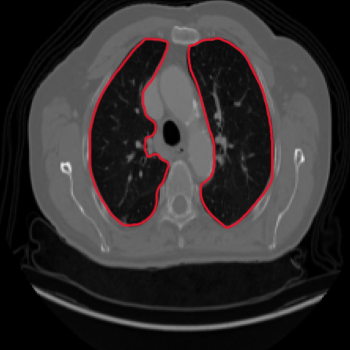

Class activation heat-map development

The final step involves the generation of feature visualisation heat-maps, elucidating the decision-making process of the trained model, and assessing its reliability. Feature visualisation is valuable for uncovering and understanding the learnt features within DL models. Zhou et al. (2016) introduced the Class Activation Mapping (CAM) method, which incorporates a global average pooling layer into a standard CNN. This innovation facilitated the identification of critical feature contributions linked to CNN’s specific predictions, shedding light on the rationale behind the model’s decisions. Furthermore, Selvaraju et al. (2017) introduced Gradient Weighted Class Activation Mapping (Grad-CAM), using gradients from the network’s final convolutional layer to generate a coarse localisation map. This map highlights influential regions within an image that contribute to the prediction of specific concepts or classes. In our study, we embraced the Grad-CAM technique on the model’s final layer to generate class-specific heat-maps. The objective is to unveil evidence of how the models arrive at predictions, with the heat-maps delineating regions of significance in the model’s prediction rationale.

Comparison using XAI techniques